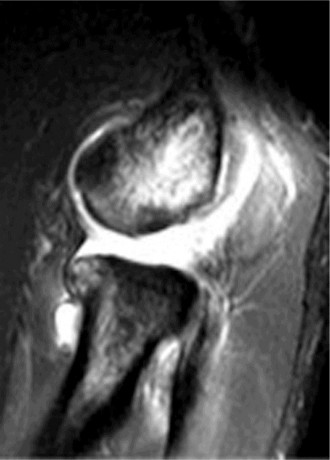

A 45-year-old carpenter presents with shoulder pain that has been ongoing for the last 3 months. He denies any significant injury. He describes night pain and significant discomfort at work. His imaging is shown in Figure 2–9. What is the most likely diagnosis?

🔍 Click to enlargeClinical Radiograph / Orthopedic Image

Figure 2–9_From Shi LL, Mullen MG, Freehill MT, et al. Accuracy of Long Head of the Biceps Subluxation as a Predictor for Subscapularis Tears. _Arthroscopy 2015;32(4):615–619.

Discussion

The correct answer is (A). Medial subluxation of the biceps tendon as seen in this MRI is commonly associated with a tear of the subscapularis tendon which attaches to the lesser tuberosity. This patient’s pain may in part be attributable to the subscapular tear and this should be evaluated for during physical examination. Supraspinatus tears (Answer B) cannot be easily visualized on axial views and are not associated with medial biceps subluxations. A labral tear and ALPSA lesion (Answers C and D) are not seen on the images provided. The question stem and MRI are not suggestive of shoulder instability (Answer E). Objectives: Did you learn...? Diagnose and treat acute rotator cuff tears?